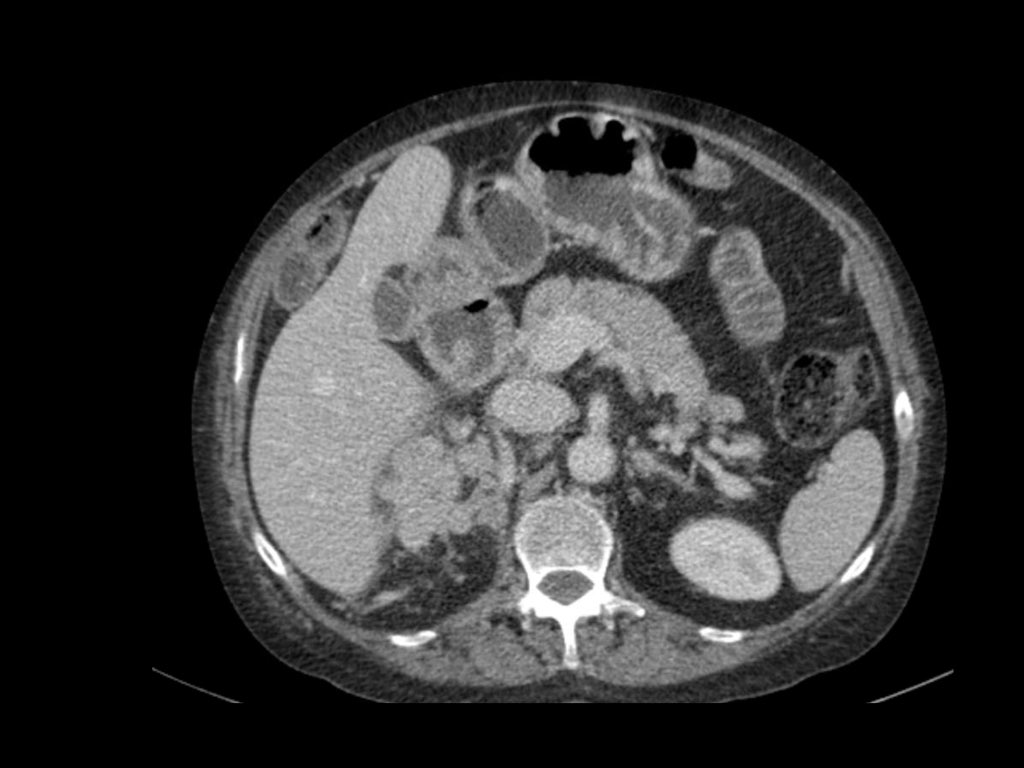

Phân giai đoạn RCC

RCC có thể xâm lấn mỡ quanh thận vượt qua cân thận và có thể lan vào tĩnh mạch thận, tĩnh mạch chủ dưới (IVC) hoặc tuyến thượng thận cùng bên.

Đối với phẫu thuật viên, điều quan trọng là cần biết có huyết khối u trong IVC hay không và liệu huyết khối có lan vào lồng ngực trên cơ hoành hay không (cần có phẫu thuật viên lồng ngực trong ca mổ).

Khoảng 25% bệnh nhân đã có di căn tại thời điểm chẩn đoán.